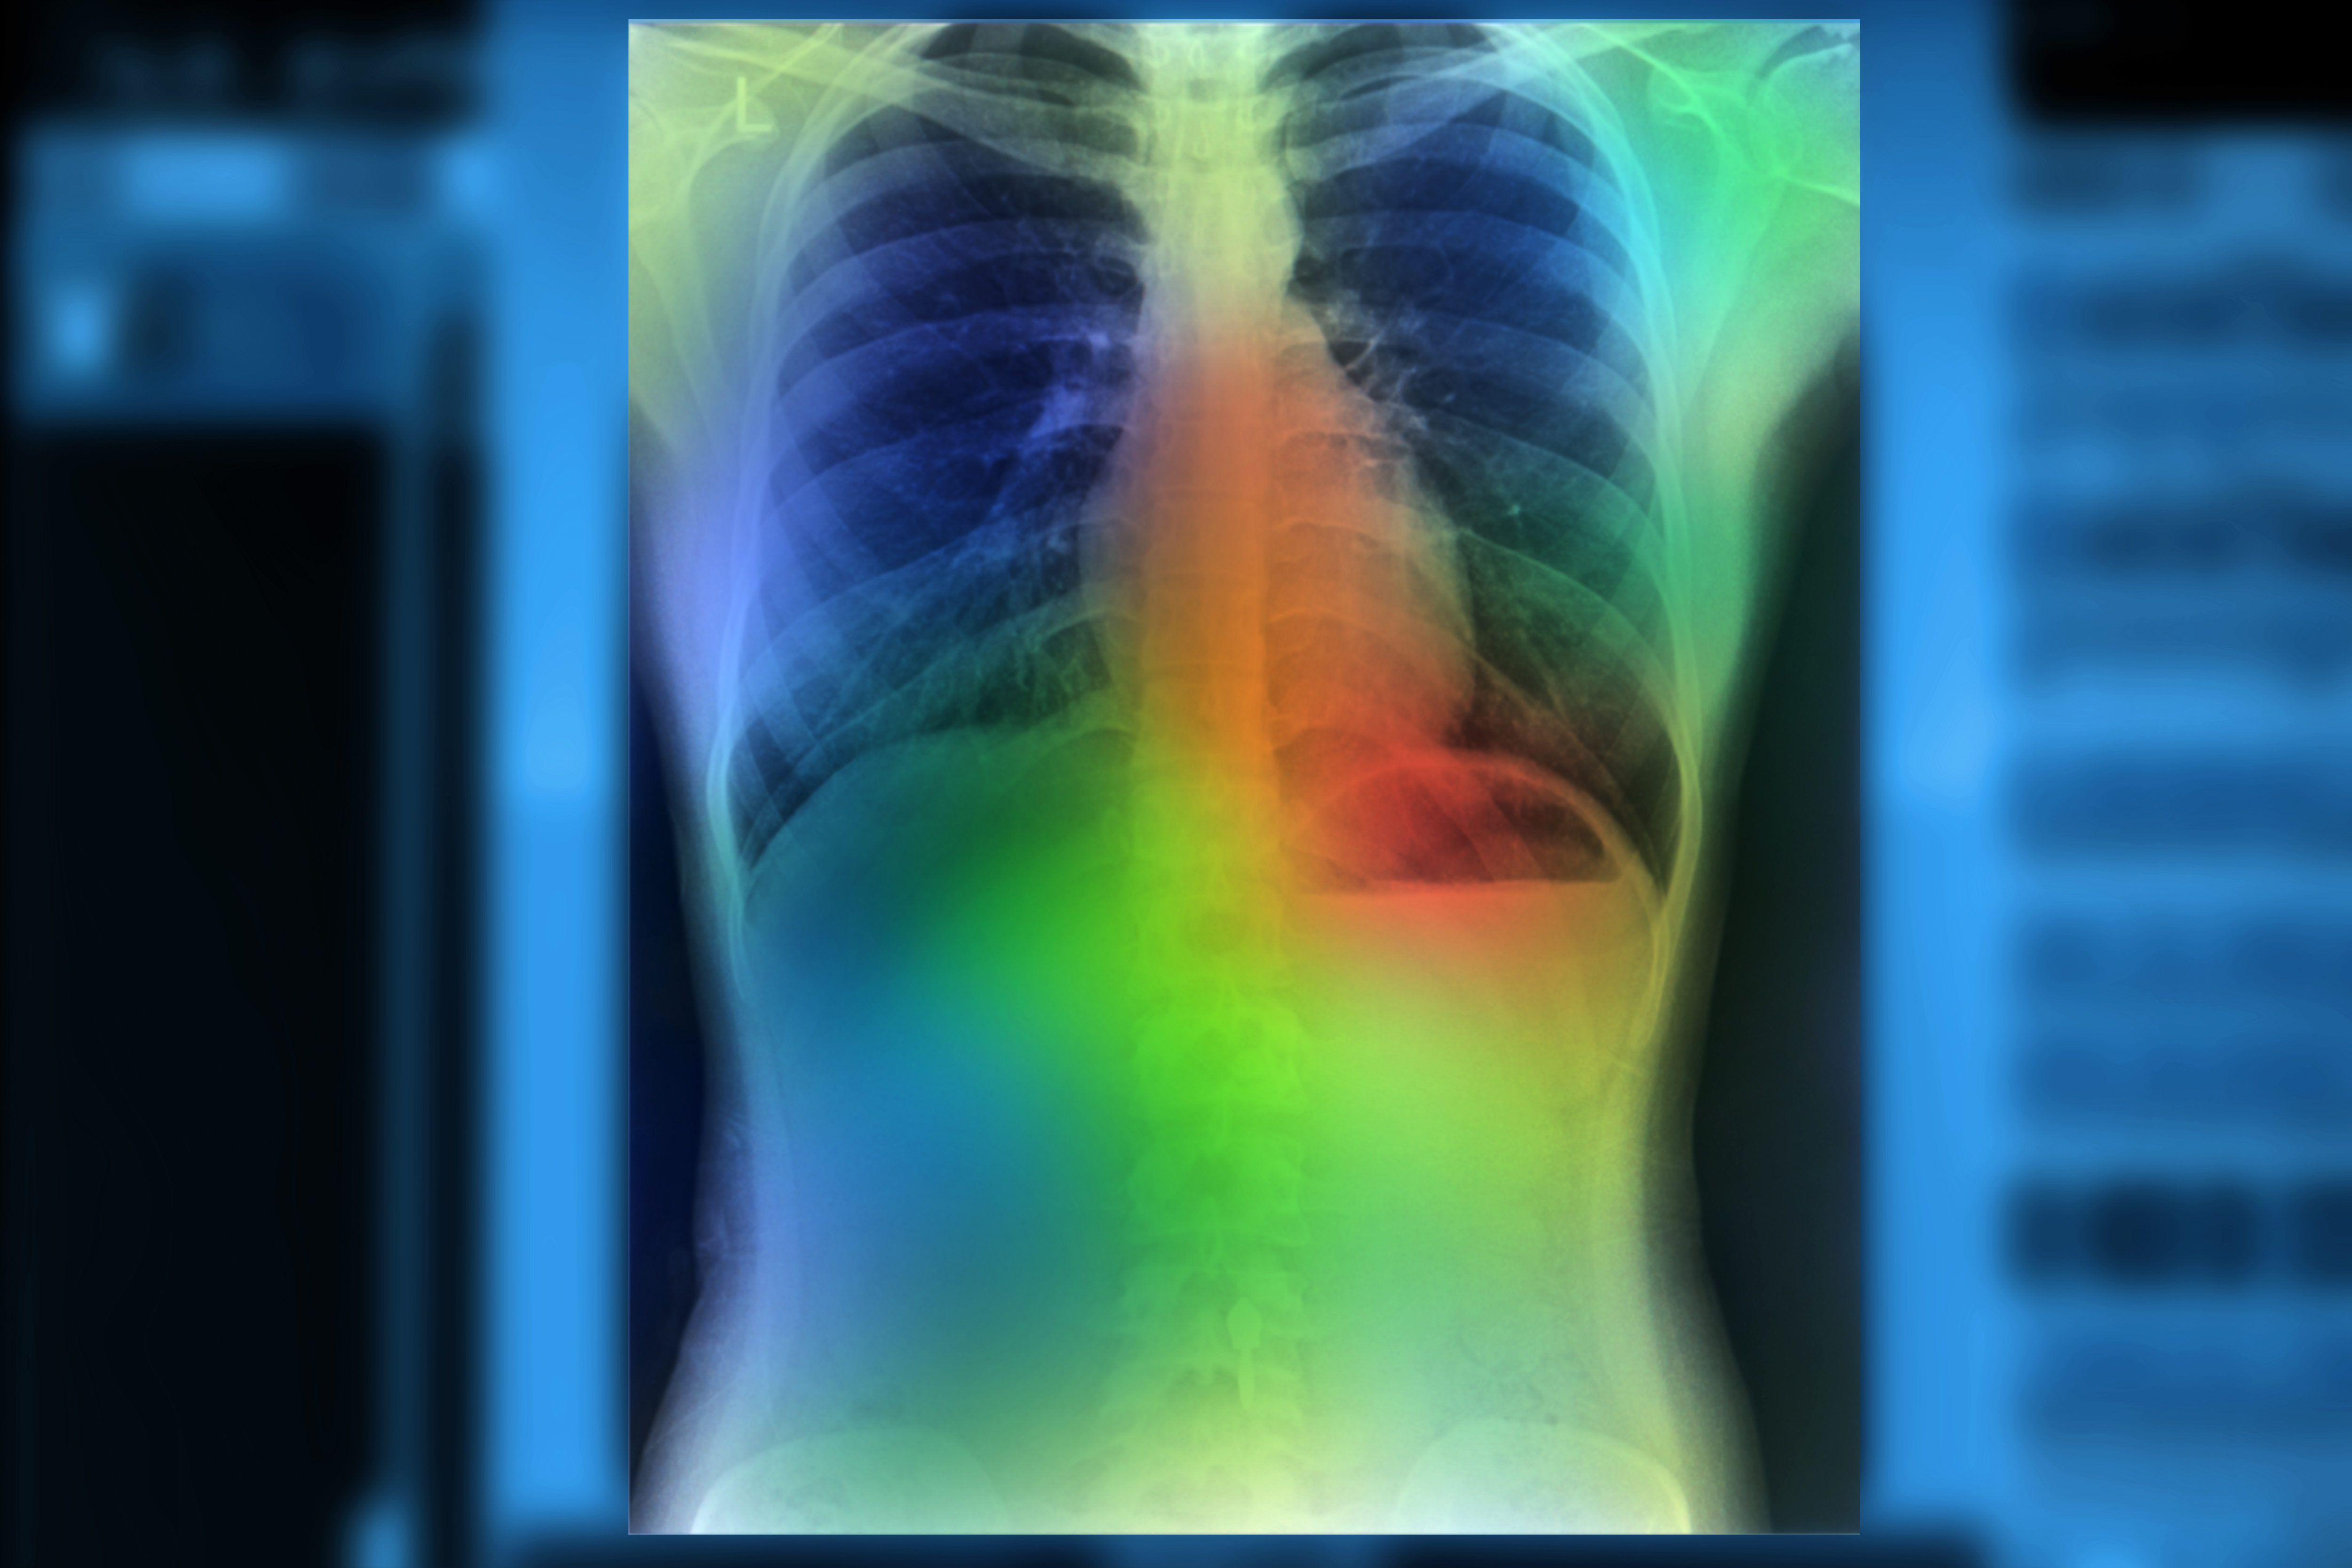

InformAI plans to use the small business innovation research (SBIR) grant for continued research and development work that will include building predictive models for heart and lung transplant outcomes and creating a clinical decision support informatics platform to assist organ transplant surgeons in matching donor organs with patient recipients, according to InformAI.